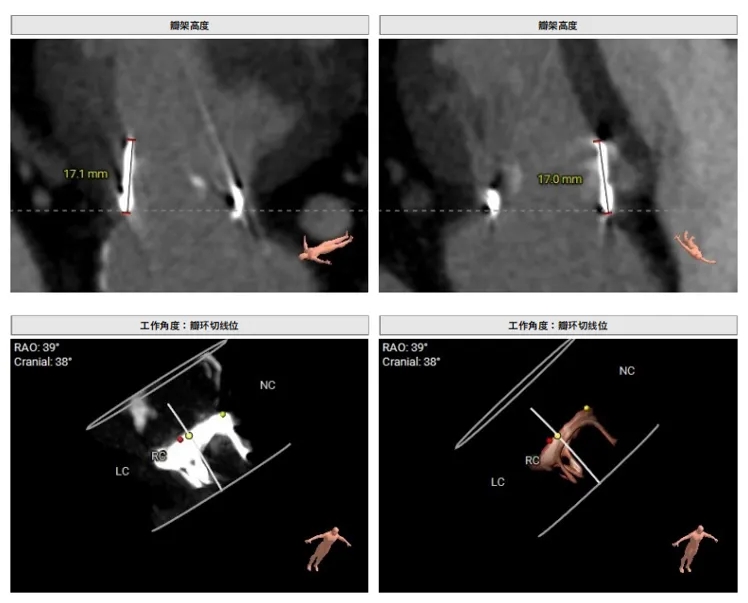

瓣架高度:约17.0mm

工作角度-瓣环切线位:RAO39°CRA38°

预选瓣膜型号:ScienCrown TAVTF25mm,备TAVTF27mm瓣膜。

选瓣依据:该二尖瓣原置换生物瓣型号未知,CT测量生物瓣瓣环周长折算直径约25.0mm,瓣架高度约17mm。

植入深度:心房侧1/5~1/4瓣架长度,约mark点平齐瓣环。